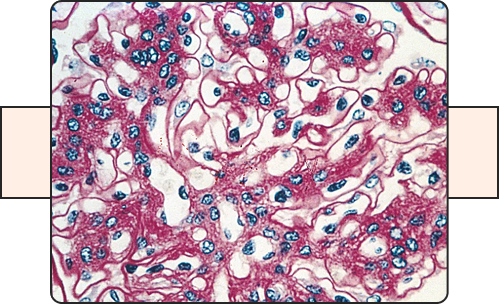

Membranous Nephropathy

This protocol aims at evaluating the efficacy of an investigational medication for adult patients with primary Membranous Nephropathy, in addition to evidence based standard of care aiming at reducing proteinuria and delay the progress of kidney disease.